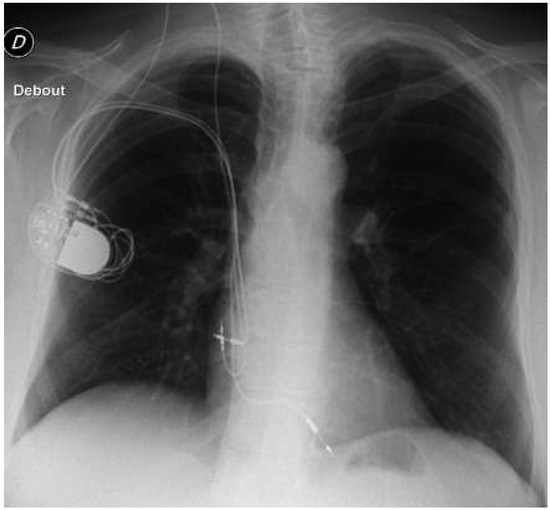

Case Presentation

Pacemaker Problem